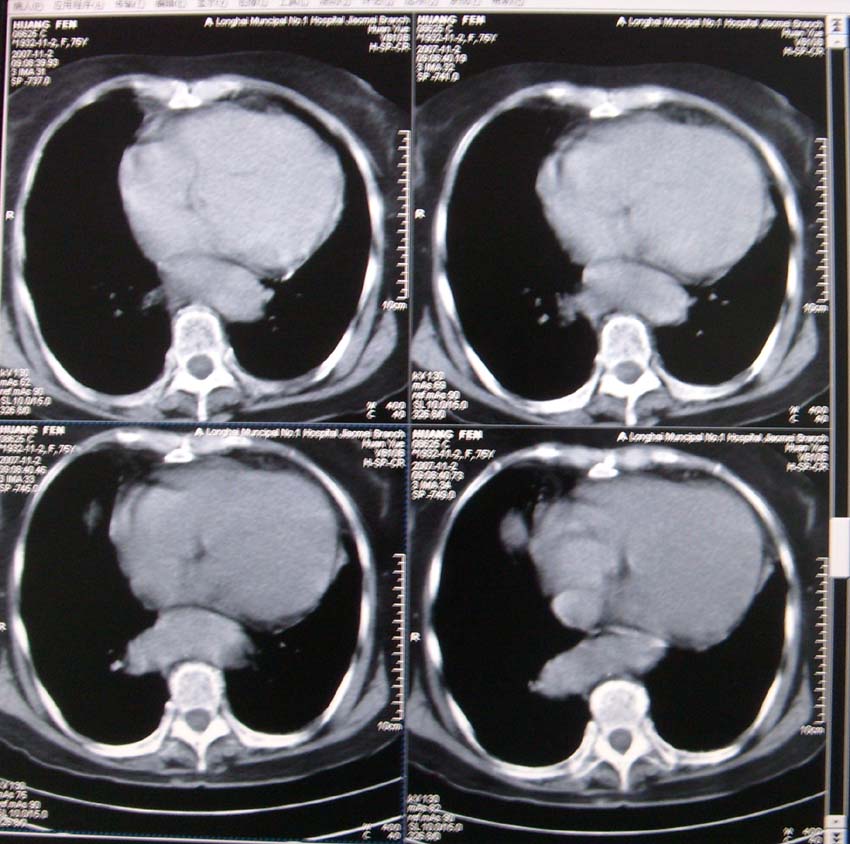

以下是引用xiaoniu在2007-11-4 12:05:00的发言:[br]这是胸主动脉迂曲延长造成的下段向右移行的影像表现,应该是:胸主动脉移行段。[br]

以下是引用nanjing在2007-11-4 12:21:00的发言:[br]降主动脉迂曲移位。